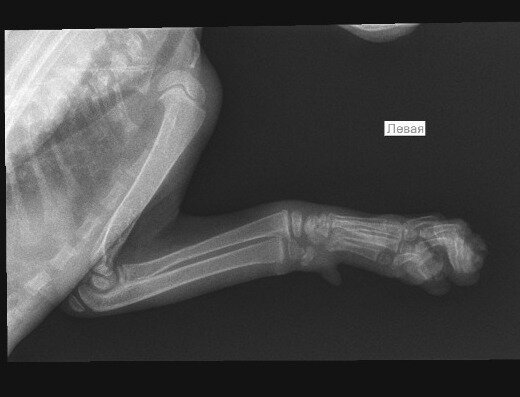

Доброго времени суток! Котенку 2 месяца, вчера поздно вечером случайно прижали дверью (не заметили как прошмыгнул), котенок сильно испугался и начал поджимать левую переднюю лапку. Наощупь серьезных повреждений не обнаружили, котенка успокоили и уложили спать. Утром попросил кушать, ковылял на трех лапках, продолжая держать левую переднюю на весу. Потом ближе к обеду разыгрался, бегал, прыгал и гонял игрушки как обычно. Решили все-таки на всякий случай показать ветеринару. Врач так же наощупь не нашёл ничего серьёзного, но сказал, что не нравится запястье, отправил на рентген. Сделали снимок в двух проекциях, косточки все целые, рентгенолог предположил, что возможен подвывих одной из маленьких косточек запястья, нужно показать кота и снимки хирургу-ортопеду. По возвращению домой котенок уснул. После сна опять начал прихрамывать, опираясь на больную лапку, и иногда поджимать её. Дело в том, что к хирургу мы попадём скорее всего не раньше конца недели. Может быть, кто-то сможет по рентген снимкам подсказать, есть ли подвывих? Нужно его вправлять? Заранее благодарю за ответы!